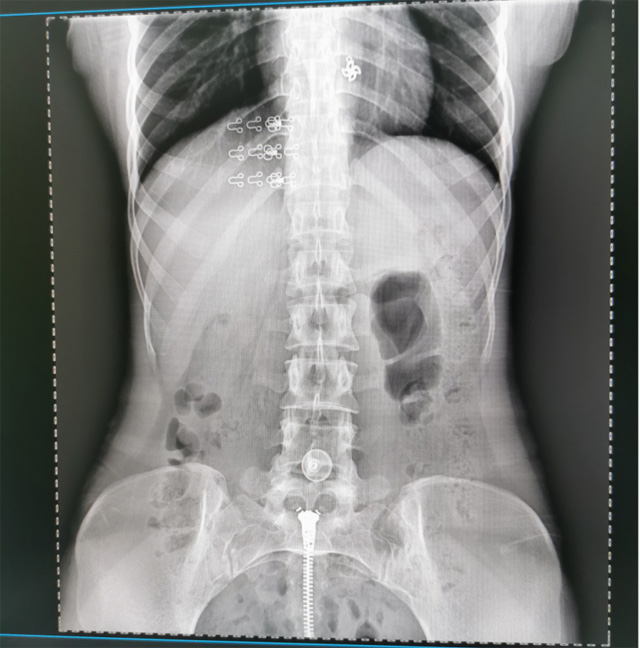

懸吊DR數字化攝影圖像質量高輻射量少誤差小滿足疾病的臨床診斷

提高醫院的影像科的醫療服務水平,滿足滿足人民群眾不斷增長的醫療需求,促進醫療技術快速發展。醫院都引進懸吊DR拍片設備新一代數字化X線攝影系統。標志著醫院的診療水平又上升一個新的臺階。懸吊DR滿足人體頭部、胸部、腹部、腰椎、四肢等部位的數字攝影檢查,可以檢查呼吸系統疾病,心臟系統的疾病、骨關節系統的疾病,子宮輸卵管造影、胃腸道造影,.有職業病體檢篩查塵肺病功能。通過DR數字化攝影,分段連續、重疊采集數字化圖像,利用軟件對圖像進行拼接的方式來獲得全脊柱、全上肢或全下肢的圖像。新設備的圖像更清晰,臨床拍攝避免患者再次搬運和移動產生的痛苦,是創傷骨折患者的福音。輻射減少受照劑量50%,后處理能力強、圖像質量高。有效降低操作難度,縮短工作流程,尤其適合大批量體檢。

具有射線劑量小、圖像清晰度高、誤差小等特點,懸吊DR已廣泛應用于各級醫療機構的體檢中心,越來越受到臨床醫生的肯定和患者的青睞。為臨床診斷工作提供更加直觀有效的技術支持,大大提高了患者就醫效率從而為患者提供更加優質的醫療服務。提高了其成像質量和臨床應用價值,并極大減少了受照輻射劑量。有效滿足了各種常見疾病的臨床診斷和治療需求。以醫療質量為根本,以優質服務為導向,竭誠為人民群眾的健康保駕護航。